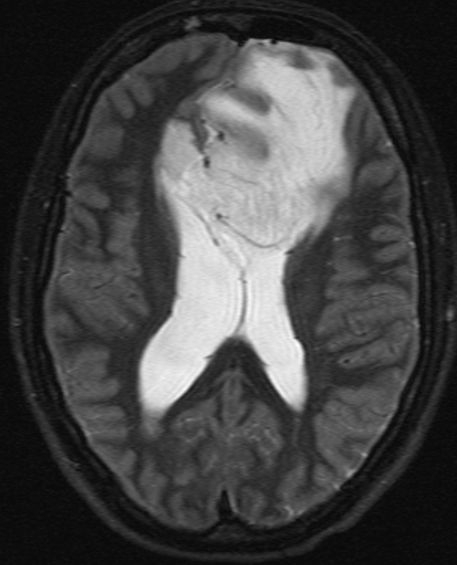

| Astrozytom II | 33jährige Frau mit einem links-frontalen Gliom Grad 2.![]()

![]() | |||||||||||||||||||||||||||||||||||||||||||||||||